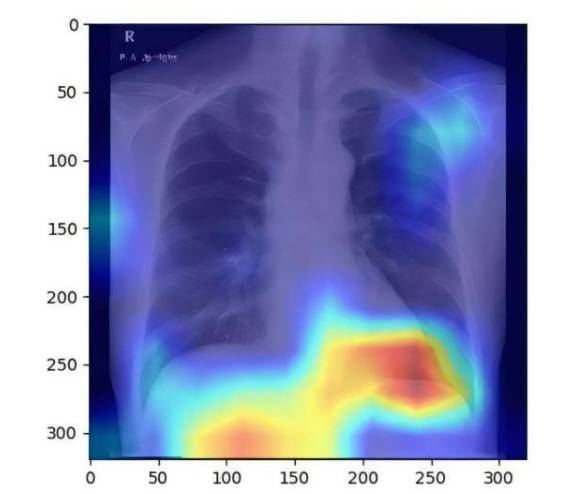

研究团队利用4,414例患者的6,599张胸部X光图像,开发出基于受控衰减参数评分的AI模型。该模型展现出优异的诊断性能,受试者工作特征曲线下面积达到0.82至0.83。内田教授表示:"这种利用现有胸部X光检查的方法,既能提高脂肪肝检出率,又能降低诊断成本。"

与传统超声波、CT和MRI等检查相比,胸部X光检查具有价格低廉、辐射剂量低且普及率高的优势。虽然该检查主要用于心肺疾病筛查,但研究证实其同样适用于脂肪肝的早期发现。这项突破性技术为脂肪肝的大规模筛查提供了新思路,有助于实现疾病的早诊早治。